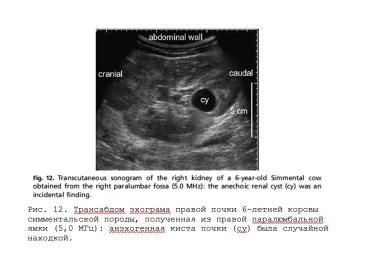

УЗИ моче-половой системы коров

Некоторое время назад разбиралась с УЗИ моче-половой системы коров (не совсем моя специализация). Надо признаться, это не рутинное исследование на фермах, потому даже в профилактических протоколах его нет. Более того, ...